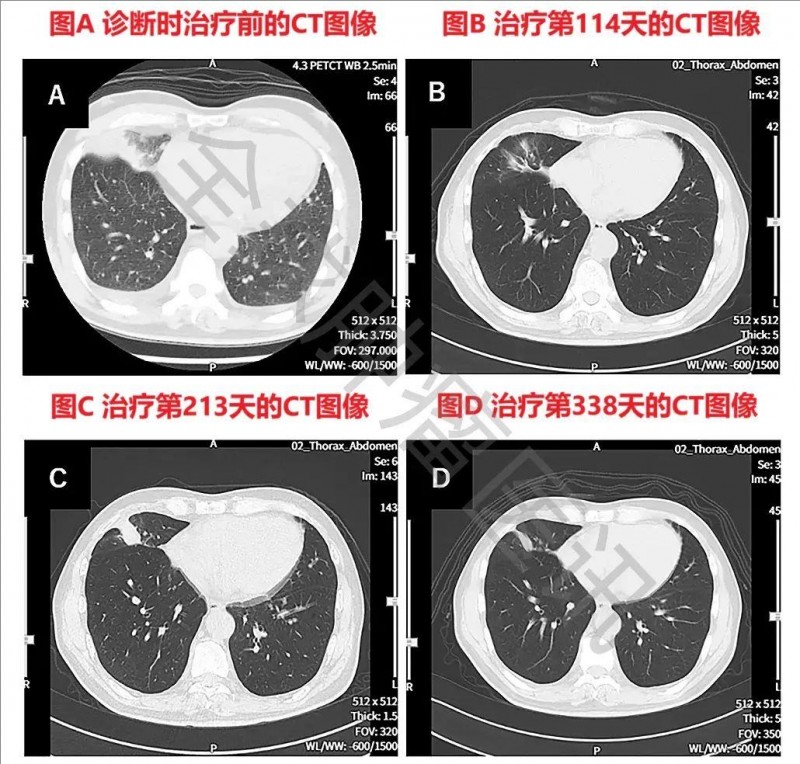

从影像检查来看,患者确诊时胸部CT显示右下肺原发性肺癌,伴有左右胸腔积液。经WT1-DC治疗114天后,肺部原发病灶近乎消失;治疗213天时,原发病灶虽有所复发;但到第338天,原发性及复发性病灶均缩小(详见下图)。

▼WT1-DC治疗前后胸部CT图像对比

▲图源“Cureus”,版权归原作者所有,如无意中侵犯了知识产权,请联系我们删除